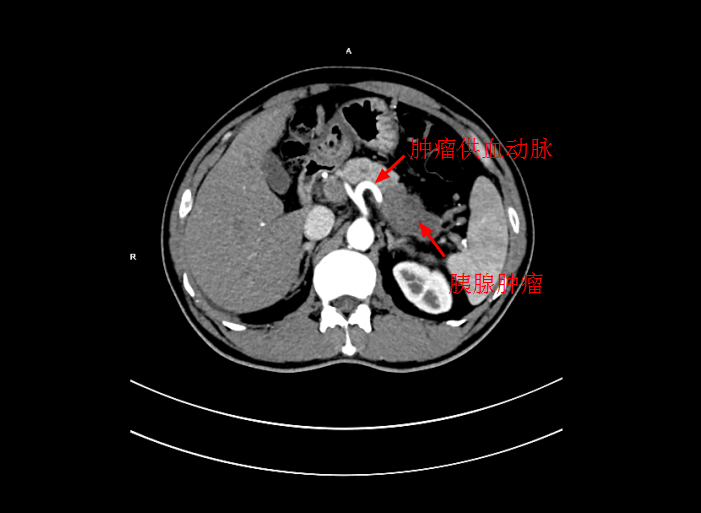

近期内三科主任李旭丹與影像科副主任胡志華攜手開展DSA下灌注化療術,治療一例局部晚期胰腺癌患者,成功将高濃度化療藥物經腫瘤的供血動脈注入到腫瘤組織中。經治療後,患者恢複良好,現已順利出院。該技術能使腫瘤組織藥物濃度達到傳統治療的10倍左右,具有殺滅腫瘤組織能力強,全身毒副作用小等優點。

4月30日下午,李旭丹主任與胡志華主任上台實施介入化療術,在DSA造影下,清晰可見胰腺腫瘤的供血動脈,專家們将微導管經股動脈穿刺送達瘤體的供血動脈,成功将化療藥物灌注至瘤體,順利完成手術。術後,患者症狀明顯好轉,并于5月4日順利出院。